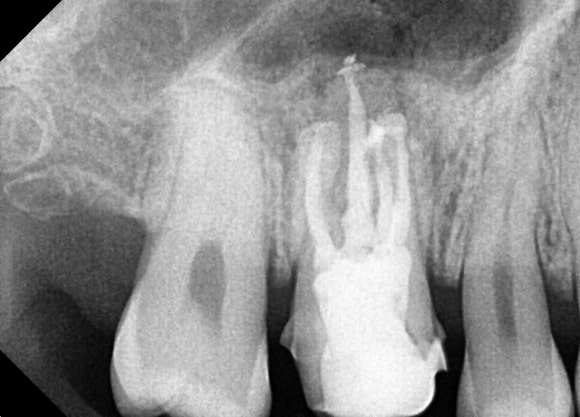

20240905

놓친 부위를 찾아서 청소해주니

막혀있던 고름이 치아를 통해

분수처럼 솟아나는 것이 보입니다.

이유를 알 수 없었던 치아와 볼 주위의

압박감과 불편감이 사라질 겁니다.